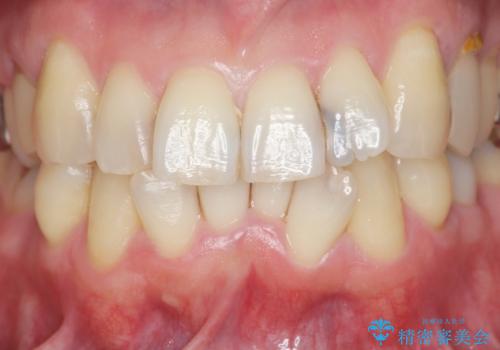

- 前歯の黒い影が大きくなってきている、と虫歯の治療を希望され来院されました。

視診、X線写真より前歯に発生した大きな虫歯が認められました。

虫歯の丁寧な除去後、今後の虫歯の2次的な発生を防ぐべく、相談の上コンポジットレジン修復ではなくジルコニアクラウンによる治療を行っていくこととしました。